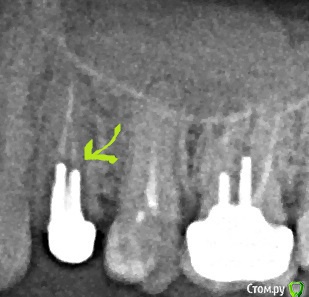

Юми Опубликовано 6 июня, 2015 Автор Поделиться Опубликовано 6 июня, 2015 Есть еще такой снимок Ссылка на комментарий

Scrabble Опубликовано 6 июня, 2015 Поделиться Опубликовано 6 июня, 2015 (изменено) Если температура-не ждите до вторника, это для организма целая вечность. Прямо завтра с утра идите. Да, 24 трещина на 99,9% Изменено 6 июня, 2015 пользователем Scrabble Ссылка на комментарий

Юми Опубликовано 6 июня, 2015 Автор Поделиться Опубликовано 6 июня, 2015 Трещина в этом месте? Ссылка на комментарий

Scrabble Опубликовано 6 июня, 2015 Поделиться Опубликовано 6 июня, 2015 (изменено) По острой боли нужно сделать что-то, а не посмотреть. Думаю, Вас в беде не оставят. Трещина не обязательно там. Изменено 6 июня, 2015 пользователем Scrabble Ссылка на комментарий